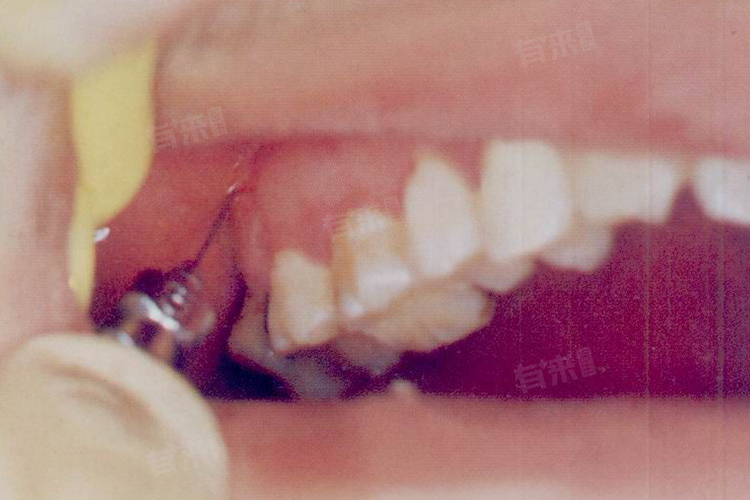

对于大多数患者,上牙槽中神经阻滞麻醉的进针点通常选择在上颌第二磨牙远中颊侧根部的口腔前庭沟处。这个位置便于医生操作,且能有效麻醉上牙槽中神经。在上颌第二磨牙尚未萌出的儿童中,进针点可以调整为第一磨牙的远中颊侧根部的前庭沟。对于上颌磨牙已缺失的患者,则可以选择颧牙槽嵴部的前庭沟作为进针点。

- 患者通常采取坐位,头微后仰,使上颌牙抬面与地面成45°,半张口,以便医生更好地观察和操作。注射器置于对侧口角,前磨牙之间,与中线成45°角。在翼下颌皱襞中点外侧3-4mm处,高于颌平面约1cm的位置作为进针点。进针时针尖应沿着上颌结节的弧形表面滑动,深约15-16mm。在触及骨壁并回抽无血后,即可注入麻醉药液。